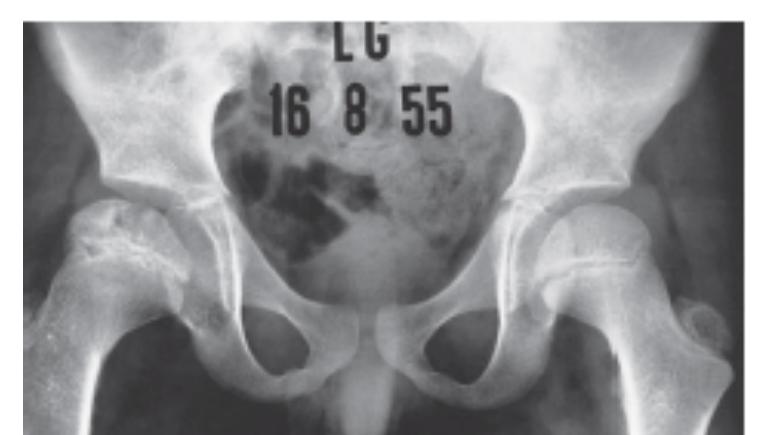

A 13 years old patient, she is known to have idiopathic scoliosis. X-ray pelvis was requested for her.

- 1. Mention the name of the sign seen the X-ray.

- Risser sign

- 2. How it can help in taking decision the management?

- By assessing potential of growth to evaluate potential deformity progression (e.g. scoliosis)

Growth Assessment Signs

Rosserโs sign

1-Describe? Rosserโs sign

2-What is clinical importance of this sign? Measure progress of bony fusion of iliac apophysis. The lower the grade, higher the potential for progression.